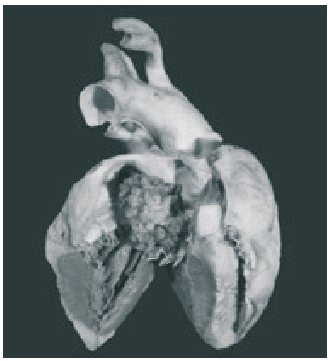

En la autopsia, se encontraron 3000 mL de ascitis serohemática. El corazón era de tamaño y peso normal. En la aurícula izquierda había una lesión exofítica, que ocupaba aproximadamente el 70% de la cavidad y midió 3 × 2,5 × 2,3 cm, era papilar, de consistencia blanda, color blanco grisáceo y se encontraba adherida a la pared medial por un pedículo de 0,3 × 0,2 × 0,1 cm (Fig. 1). Microscópicamente se identificó una neoplasia de aspecto mixoide, poco celular, mezclada con glándulas, las cuales se encontraron en aproximadamente 20% del tejido examinado. Las glándulas estaban formadas por epitelio cúbico, con núcleos pequeños, ovoides, de localización basal, con escasas células caliciformes. Con las tinciones de PAS (Fig. 2) y hierro coloidal se demostró positividad para mucosubstancias. El resto de la lesión estaba constituida por células fusiformes o estelares, inmersas en una matriz mixoide. De forma aislada, había macrófagos con hemosiderina y células gigantes multinucleadas. Las reacciones de inmunohistoquímica en el componente glandular resultaron positivas para antígeno carcinoembrionario y citoqueratina 7 y negativas para Hepat y a-fetoproteína (Fig. 3).

Fig. 1. Aurícula izquierda con lesión papilar que ocupa gran parte de la cavidad.